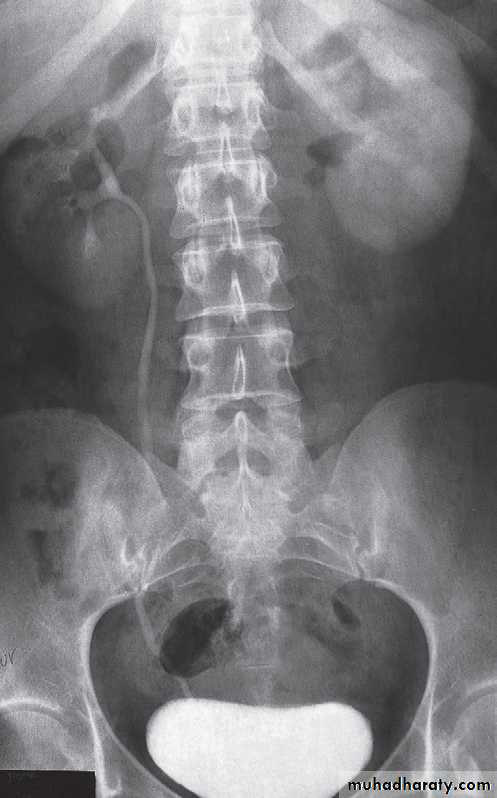

X-ray examinations :Most urinary calculi are calcified and show varying density. Many are uniformly calcifiedbut some, particularly bladder stones, may be laminated. Only pure uric acid and xanthine stones are radiolucent on plain radiography, but they can be identified at CT or ultrasound .Small renal calculi are often round or oval; the larger ones frequently assume the shape of the pelvicaliceal system and are known as staghorn calculi .

Computed tomography without intravenous contrast medium is exquisitely sensitive for the detection of calculi.

It is used in place of IVU for the detection and precise anatomical localization of stones prior to treatment in most centres